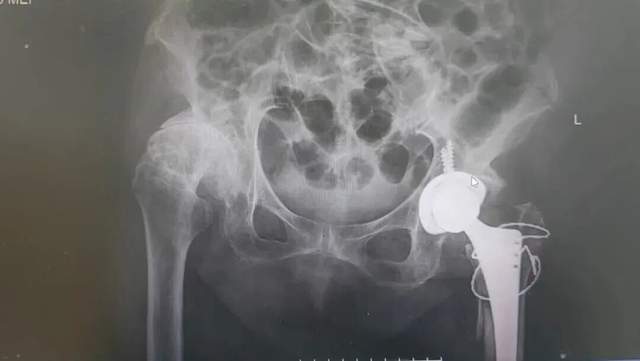

入院后完善检查诊断为:左股骨粗隆间粉碎性骨折合并股骨头坏死、重度骨质疏松

面对90岁高龄,基础病多、身体耐受差等重重困境,如何治疗成为关键,保守治疗无异于“坐以待毙”,微创固定则可能“治标不治本”,宁乡市中医医院骨伤关节外科团队以姜奶奶长远生活质量为核心,经过严密评估,多学科会诊,反复沟通,选择了“全髋关节置换”方案。

确定方案后,骨伤关节外科主任肖放军带领团队,在老人脆弱的骨骼与组织间精准操作,成功将人工关节安置到位,在毫米之间架起“生命轴承”。

图片

(▲术前CT检查)